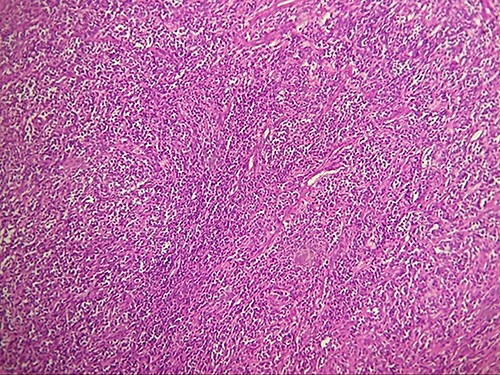

Macroscopically, the tumor was whitish, fleshy, firm, with a polylobed surface and harboring foci of necrosis. Histological examination showed densely cellular spindle cell proliferation without evidence of differentiation, with focal nuclear pleomorphism and few foci of tumor necrosis (<50%). Mitotic activity was high, estimated at 13 mitoses/10 fields at high power. (Figs 2–4) An exhaustive immunohistochemical study was necessary to classify this tumor (Cytokeratin AE1/AE3, Melan A, Epithelial Membrane Antigen (EMA), PS100, Smooth Muscle Actin (SMA), H-Caldesmone, Desmin, Myogenin, CD34, CD31, Chromogranin, Synaptophysin, CD56, P63, Beta-Catenin, STAT6 and SOX10). Tumor cells expressed SOX10 intensely and diffusely (Fig. 5), and PS100 focal (Fig. 6). The other markers were not expressed and the Ki 67 proliferation index was estimated at 60%.

Malignant tumors of the peripheral nerve sheaths are lesions that can sometimes be responsible for expansion of the nerve from which they originate. Depending on the stroma and cellularity, tumors can be fleshy, fibrous or gelatinous. Macroscopically, MPNSTs are large masses, producing swelling of major nerves. Microscopically, most MPNSTs have a richly cellular fasciculated architecture made up of generally monomorphic spindle cells with eosinophilic cytoplasm of hyperchromatic rounded or oval nuclei and indistinct cell boundaries. There is often some degree of nuclear pleomorphism. Mitotic figures are more often found in intermediate and high-grade tumors and therefore more rarely in low-grade MPNST. Some cases of MPNST show high cellularity and diffuse throughout the tumor, with a pattern of fascicular growth similar to fibrosarcoma or monophasic synovial sarcoma. Most often, however, tumors are composed of relatively hypocellular areas alternating with hypercellular areas showing perivascular emphasis, resulting in a mottled appearance at low magnification. The extracellular matrix in less cellular areas is usually myxoid, which can be abundant in up to 10% of cases. Clusters of small rounded blood vessels are commonly seen in high-grade tumors [1].